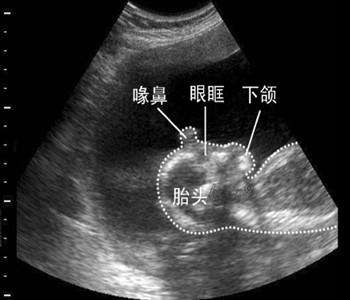

1、月份小的胎儿

针对月份很小的胎儿,一般在流产时都采取药物的方式,用药物将胎儿“扼杀”在女性的腹中,然后再排出女性的身体。这种被排出的胎儿,最终归宿就是流进了马桶里,随着旋转的抽水被带进了下水管、地下水道,再也看不见。